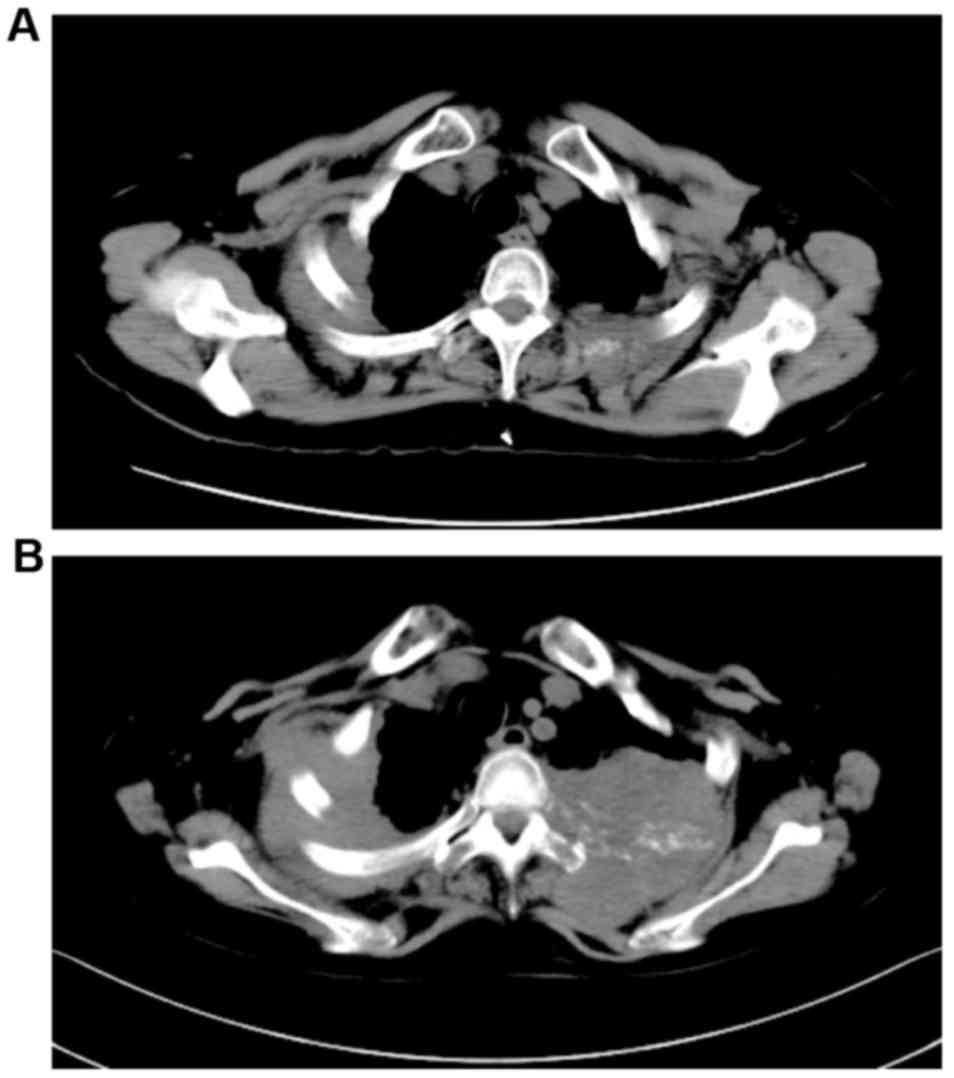

Figure 4.

Time-dependent change in the radiological findings for Case 2. (A) The CT scan image of pleural thickening at the initial appointment. (B) The CT scan of pleural thickening at the time of readmission. CT, computed tomography.